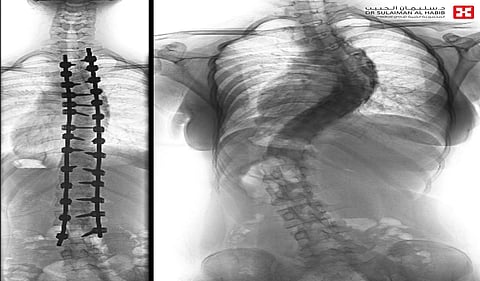

أنهى مستشفى الدكتور سليمان الحبيب بالفيحاء في جدة، معاناة شابة عمرها "17" سنة، مصابة بانحرافٍ مضاعفٍ في العمود الفقري، ونجح الفريق الطبي الذي قاده د. صلاح الدين خليفة؛ استشاري جراحة العظام والعمود الفقري، في تقويم العمود الفقري وتثبيت ودمج الفقرات، مع تجميل للقفص الصدري.

وقال د. خليفة؛ إن المراجعة جاءت إلى المستشفى وهي تشتكي من انحناءٍ جانبي للعمود الفقري منذ عام، وبدأت تعاني أخيراً من أعراض متفاقمة، حدَّت من حركتها وقدرتها على ممارسة حياتها بصورة طبيعية، وأُجريت لها التحاليل والفحوصات الطبية الدقيقة، التي بيّنت إصابتها بحالة انحراف "جنف" يبلغ "80" درجة في فقرات الصدر، وبعد دراسة الحالة أخضعها الفريق الطبي لعملية جراحية معقدة، تمّ فيها تقويم العمود بالشرائح المعدنية التايتانيوم والكوبالت كروم والطعوم العظمية الصناعية وتثبيت ودمج الفقرات، ومع استخدام تقنية تكسير وتعديل الأضلاع الصدرية، للمساعدة في التقويم، إضافة إلى تجميل القفص الصدري. شارك في العملية التي استمرت "6" ساعات، فريق تخدير متمرس، وفريق تمريض ماهر، إضافة الى استخدام مجموعة من أحدث الأجهزة الطبية، كمراقبة الأعصاب التي أسهمت مع الكوادر الطبية عالية الكفاءة والتأهيل بالمستشفى في إنجاحها.

وأوضح د. خليفة؛ أن جهود الفريق الطبي تكللت ولله الحمد بالنجاح، ونقلت المراجعة إلى العناية المركّزة وبقيت ساعات عدة تحت المراقبة، ثم حُولت إلى الجناح العادي. وتحسنت حالتها باطراد، إذ استطاعت المشي بعد أقل من "24" ساعة من العملية، مع فريق العلاج الطبيعي المتمرس، واستعادت القدرة على الاستلقاء والنوم على ظهرها؛ فضلاً عن القوام والمظهر الطبيعي، بعد تعديل وضعية الحوض والكتف، كما أن طولها مع النجاح للتعديل زاد نحو "4" سم، وخرجت من المستشفى وهي بصحة جيدة، مضيفاً أنها ستتحسّن وتستعيد كامل عافيتها، إن شاء الله، بعد استكمال البرنامج العلاجي المخصّص لها.